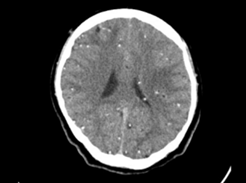

Figura 2-3. TC simple de cráneo: cortes axiales, coronales y sagitales.

Hallazgos Fig 3: Se observan incontables imágenes nodulares cálcicas micronodulillares, que miden entre 2 mm y 5 mm, localizadas en todo el parénquima, de origen parasitario, en la región parietal se aprecia formas nodulares coloides en número de 2 a cada lado de la línea media. Además presencia de calcificaciones fisiológicas en la glándula pineal, hoz y plexos coroideos.  Informe:  Nataly Xiomara Bastidas Mora.

§  Estadio nodular-granulomatoso de neurocisticercosis, se asocia a signos de edema periférico adyacente de predominio supratentorial

§  Neurocisticercosis a forma nodulillar calcificada

§  Neurocisticercosis nodular coloide activa parietal bilateral

Se realizó interconsulta en las áreas de oftalmología, infectología y neurología quienes establecen su diagnóstico, exámenes complementarios y tratamiento respectivo: se solicitó una TAC simple de encéfalo (Figuras 3-4), evidenciándose múltiples calcificaciones intracraneales, sugestivas de neurocisticercosis en varias etapas, e hipodensidad mal definida en región parietal izquierda, considerada edema cerebral que sugieren un proceso de autoinfección en la paciente, sumado a un cuadro de atrofia del nervio óptico con consecuente pérdida irreversible de la visión asociada a la neurocisticercosis. Determinando el diagnóstico de cisticercosis del sistema nervioso central.

Se estableció el diagnóstico de neurocisticercosis mediante tomografía computarizada simple de encéfalo en cuyos hallazgos se evidenció imágenes nodulares cálcicas, que miden entre 2 mm y 5 mm, localizadas en todo el parénquima, y en la región parietal se aprecian formas nodulares coloides en número de 2 a cada lado de la línea media.